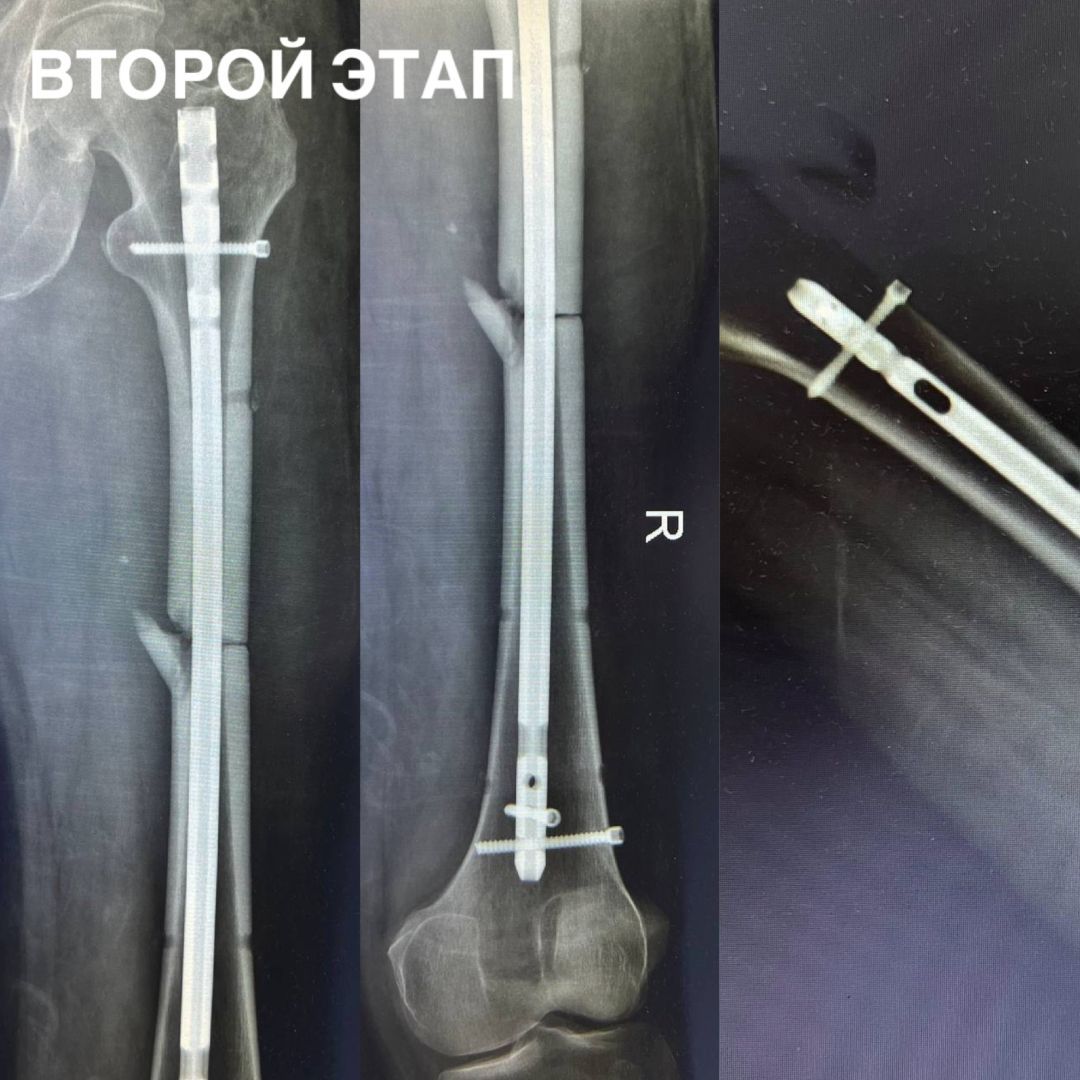

• Ставропольские врачи спасли мужчину после падения с 7-метровой высоты

В Ставрополе специалисты городской клинической больницы СМП помогли 55-летнему мужчине. Во время падения с 7-метровой высоты он получил открытый оскольчатый перелом правой бедренной кости со смещением костных отломков.

Специалисты незамедлительно обработали рану и стабилизировали состояние больного, после чего провели интрамедуллярный блокируемый остеосинтез бедренной кости. Данная методика обеспечила надежную фиксацию фрагментов кости и позволила как можно раньше начать реабилитацию.

В настоящее время пациент готовится к выписке для дальнейшего восстановления амбулаторно. Операцию провели заведующий отделением сочетанной травмы Артур Эдуардович Апагуни и врачи-травматологи-ортопеды Виктор Викторович Посух и Михаил Евгеньевич Даньшин, рассказали в Минздраве Ставрополья.

Фото: Минздрав Ставропольского края